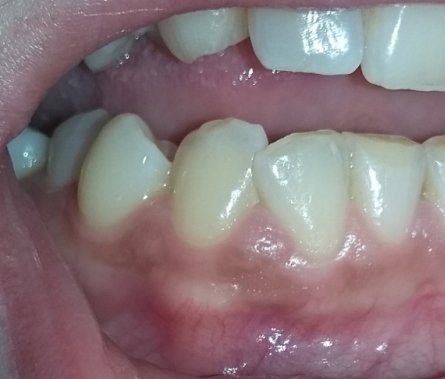

Подскажите, пожалуйста. Болела десна около недели, незначительно. Позже образовался какой-то шарик, похожий на прыщик. А после, во время еды что-то стало мешать и вот появилось непонятное новообразование из десны. На ощупь твердое, беспокоит во время приема пищи.

Очень сложно определить, но все Ваши симптомы говорят и свищевом выходе. То есть, на верхушках зуба имеется воспалительный процесс.